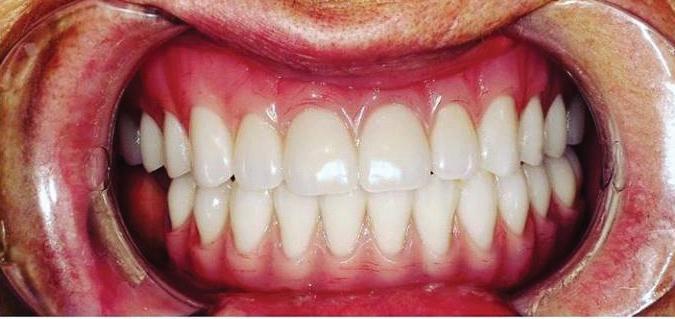

Can just four implants replace all of the teeth on the top or the bottom of your mouth? Thanks to advances in dental implant technology, that answer is a resounding yes.

Believe it or not, tooth loss is extremely common among adults, especially as we age. In fact, more than 35 million people in America are missing all of their upper and/or lower teeth. Rather than living with the discomfort and hassles of dentures, many people are opting for what is called “all-onfour” dental implant restoration.

able technique for replacing teeth, you should first understand what a dental implant is. An implant is a small titanium screw that fits inside your jawbone and replaces the root-part of a missing tooth. Minor surgery is required to insert the implants. Once the implant is in place, a crown is attached to give you a highly realistic-looking and functional prosthetic tooth.

Here’s where it gets really interesting: You do not need a dental implant for each and every one of your missing teeth. All you need is four precisely placed implants on the top of your mouth, and four on the bottom, to restore your full smile. That’s the beauty of the all-on-four. And because the implant is made of titanium, it has the unique ability to fuse to living bone and function as part of it. So eventually, the dental implant becomes part of the jawbone and serves as a strong, long-lasting foundation for your new teeth.

this bone fusion has another important benefit: it prevents future bone loss in the jaw. This helps to maintain a more youthful facial structure – and better oral health. But perhaps the biggest surprise about the all-on-four is how quickly it can transform your life.

What’s The All-On-Four Dental Implant Procedure Like?

It can be scary to get implants for the first time. Most of that fear is probably due to the uncertainty, so here is the step-by-step process for getting an All-On-Four dental implant.

First, your dentist will want to make sure your comfortable, so either local or general anesthesia will be administered.

Second, the dentist or surgeon will prepare your mouth for the implants, which involves removing your remaining teeth that are failing. They will then remove any diseased or infected tissue from your jaw and gums.

Next, they will begin the implantation process. This means they will

insert the titanium screws into your jawbone. Most likely, they will place two implants toward the front of your mouth and two towards the back of your mouth so the “anchors” can evenly bare the force of the denture.

After the implants have been placed, they will thoroughly clean the surgical sites and suturing all the incisions. Then you’ll be taken to a recovery room where you can relax and take time to wake up from the anesthesia.

How Do You Know If The All-On-Four Procedure Is The Right Option For You?

At your All-On-Four consultation, you’ll receive a 3D CT Scan. This scan will help determine if you need implants and assist your doctors in creating your treatment plan. So if you want to learn more about dental implants, simply schedule a consultation with an All-On-Four provider. It’s the best way to find out how dental implants can change your life.